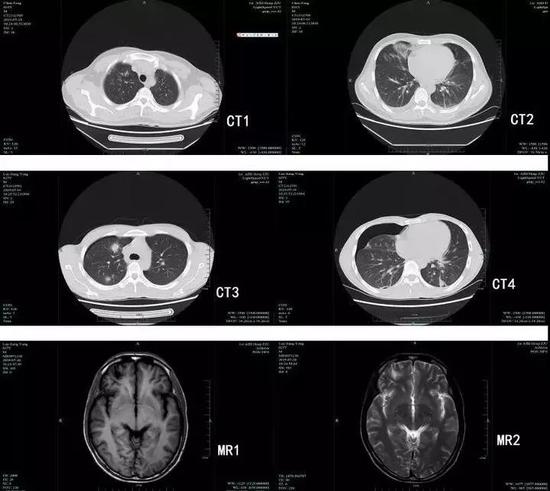

肺吸虫感染后的肺部团块影和颅内软化灶

果然,经过寄生虫检测,两人均为卫氏肺吸虫抗体阳性,均在腹部和肺部发现肺吸虫,骆某更是在脑子里发现肺吸虫囊性灶,比较严重。幸好两人发现及时,并且就医及时,经过药物治疗后康复出院,没有留下后遗症。